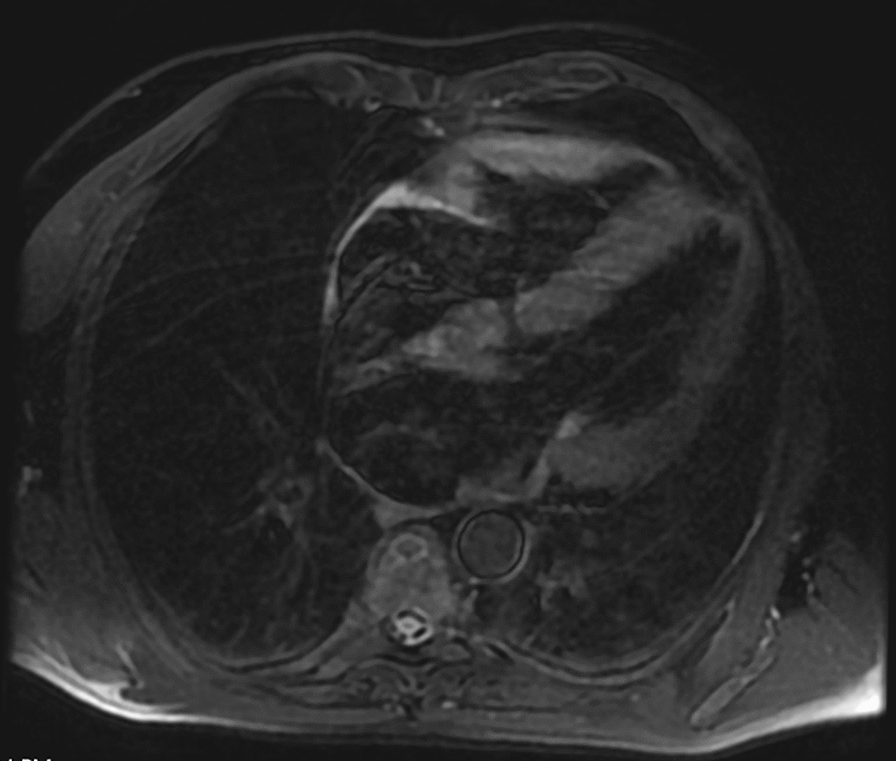

Case presentation: A 66-year-old Mexican male patient with a family history significant for hereditary amyloidosis presented with intermittent chest pain, shortness of breath, and neurological symptoms. An echocardiogram done at an outside hospital showed an ejection fraction of 55-60% with grade 2 diastolic dysfunction. A technetium pyrophosphate scan was used to make the diagnosis of transthyretin amyloidosis, and genetic testing showed that the patient was heterozygous for p.G67A (also known as c.2000G > C) pathogenic mutation in the transthyretin (TTR) gene. Due to these findings the patient was started on tafamidis free acid 61 mg daily and vutrisiran (Amvuttra) injections. He was also given vitamin A supplementation to prevent vutrisiran-associated vitamin A deficiency, which is a known side effect.